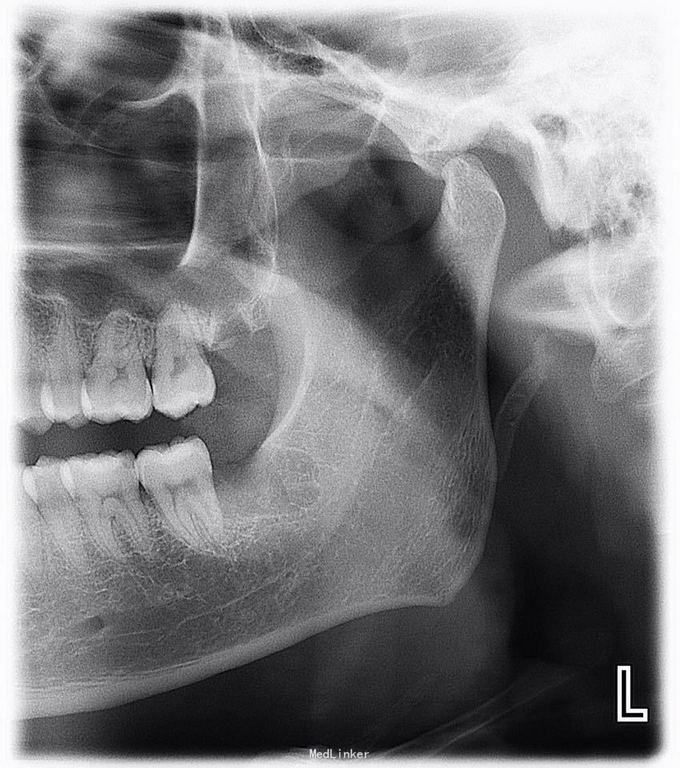

体检时发现左下智齿阻生,要求拔除,想微创一点就没有翻瓣没有去骨,硬是把牙一块一块分开挖出来的,当然了耗时我一个小时,不知道这样对不对,还是直接翻瓣去骨后分分钟敲出来对患者更好